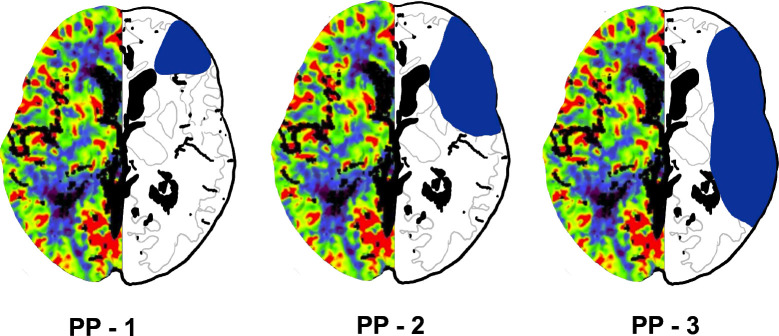

Methods: This retrospective study included 201 patients with acute ischaemic stroke, categorised into two groups: those with M1 segment occlusions (n=114) and those with distal medium vessel occlusions (n=87). We analysed multimodal stroke CT imaging and clinical data, focusing on the occlusion site, hypoperfusion extent and basal ganglia involvement. Patients with tandem stenosis or multiple acute occlusions were excluded. Perfusion patterns were categorised into three types (PP-1, PP-2 and PP-3) based on the extent of hypoperfusion. Statistical analysis explored associations between the occlusion site, perfusion pattern and collateral status.

Results: Among the 201 patients (mean age 75±14 years, 86 men), PP-1 was observed in 36.8% of patients (74/201), PP-2 in 27.4% (55/201) and PP-3 in 35.8% (72/201). The distribution of PP varied significantly by occlusion site (p<0.0001). Distal medium vessel occlusions were associated with PP-1 in 78.4% of cases (58/74), while PP-3 was most prevalent in M1 occlusions (90.3%, 65/72). The contingency coefficient revealed that occlusion location had a stronger association with the perfusion pattern (c=0.556) than collateral type (c=0.245). However, 21.6% of M1 occlusions (16/74) showed a PP-1 pattern and 9.7% of distal medium vessel occlusions (7/72) exhibited PP-3. Basal ganglia infarction presence was a reliable indicator of M1 occlusion with a 94% likelihood.